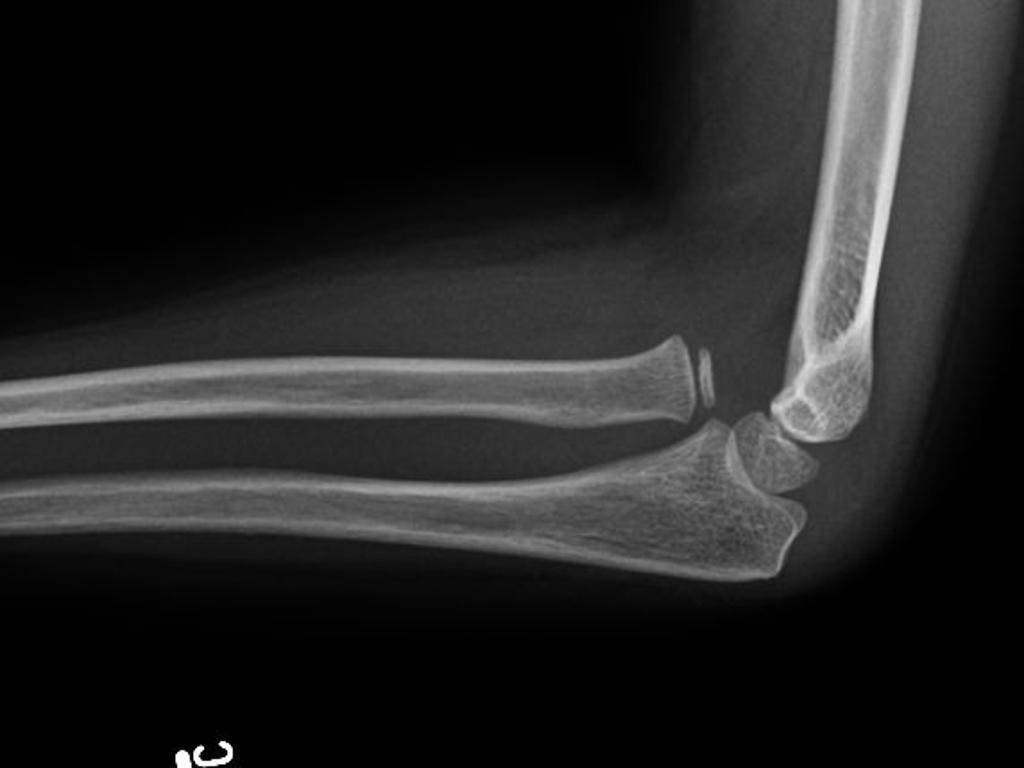

Order of elbow centres of ossification

A

• Capitellum

• Radial head

• Internal epicondyle

• Trochlea

• Olecranon

• External epicondyle

• Seen at 1, 3, 5, 7, 9, 11 years of age

• Radial head dislocation

• Check radiocapitellar line - line through radial neck should always intersect the capitellum in any view

• Often dislocated anteriorly

https://radiopaedia.org/articles/radiocapitellar-line

Approach to elbow x-ray

• CRITOE

• Alignment

• Anterior humeral line should intersect middle third of capitellum (if not, think supracondylar fracture)

• Radiocapitellar line (line through radial neck should always intersect capitellum, if not think radial head dislocation)

• Effusion

• Posterior fat pad - always abnormal

• Anterior fat pad - abnormal if massive

• Bone cortex of all bones for irregularities

• Monteggia fracture dislocation

• Fracture of ulnar shaft with radial head dislocation

• Note radiocapitellar line